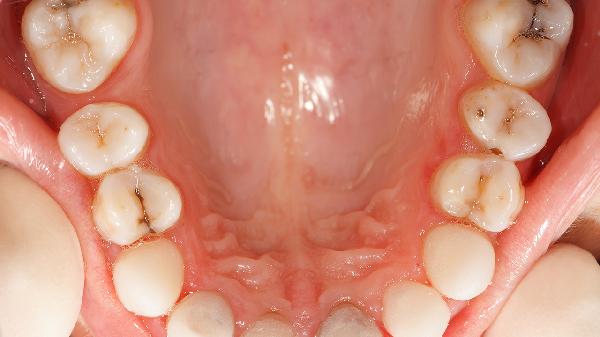

氟斑牙可能由長(zhǎng)期攝入過(guò)量氟化物、飲用水氟含量超標(biāo)、使用含氟牙膏不當(dāng)、高氟地區(qū)生活、兒童牙齒發(fā)育期氟暴露等原因引起。氟斑牙主要表現(xiàn)為牙齒表面出現(xiàn)白堊色斑塊、黃色或棕色著色,嚴(yán)重時(shí)伴隨釉質(zhì)缺損。

長(zhǎng)期過(guò)量攝入氟化物會(huì)導(dǎo)致氟在牙釉質(zhì)沉積,干擾釉質(zhì)形成過(guò)程。這種情況多見(jiàn)于日常飲食中氟含量較高的地區(qū),如經(jīng)常食用含氟量高的海產(chǎn)品或茶葉。預(yù)防措施包括控制高氟食物攝入量,定期監(jiān)測(cè)飲用水氟濃度。對(duì)于已形成的輕度氟斑牙,可采用滲透樹(shù)脂修復(fù)技術(shù)改善外觀。

飲用水中氟化物濃度超過(guò)1毫克每升時(shí)可能引發(fā)氟斑牙。我國(guó)部分高氟地區(qū)的地下水含氟量可達(dá)2-10毫克每升,遠(yuǎn)超過(guò)安全標(biāo)準(zhǔn)。這種情況需要安裝反滲透凈水設(shè)備降低飲水氟含量。中度氟斑牙患者可考慮牙齒漂白治療,常用藥物有過(guò)氧化脲凝膠。

兒童在牙齒發(fā)育期吞咽含氟牙膏可能導(dǎo)致氟斑牙。6歲以下兒童每次使用牙膏量應(yīng)不超過(guò)豌豆大小,并需在家長(zhǎng)監(jiān)督下刷牙。已出現(xiàn)氟斑牙的兒童可使用氟斑牙專(zhuān)用修復(fù)牙膏,如含羥基磷灰石成分的修復(fù)型牙膏。嚴(yán)重病例需在牙科進(jìn)行微研磨聯(lián)合再礦化治療。

長(zhǎng)期居住在高氟地理環(huán)境是氟斑牙的重要誘因。這類(lèi)地區(qū)土壤和空氣中氟含量較高,通過(guò)多種途徑進(jìn)入人體。預(yù)防措施包括改善居住環(huán)境,使用除氟設(shè)備。對(duì)于伴有釉質(zhì)缺損的重度氟斑牙,可采用瓷貼面或全冠修復(fù),常用材料有二氧化鋯全瓷冠。

兒童在牙齒鈣化期對(duì)氟化物特別敏感,此時(shí)過(guò)量氟攝入會(huì)造成不可逆的釉質(zhì)發(fā)育不全。這種情況可能與同時(shí)服用氟補(bǔ)充劑和飲用含氟水有關(guān)。治療上可選擇滲透樹(shù)脂聯(lián)合冷光美白,必要時(shí)進(jìn)行貼面修復(fù)。常用藥物包括氟化鈉凝膠和過(guò)氧化氫美白劑。

預(yù)防氟斑牙需注意控制氟攝入總量,兒童期特別要避免多重氟暴露。建議定期進(jìn)行口腔檢查,發(fā)現(xiàn)早期氟斑牙及時(shí)干預(yù)。日??墒褂煤}磷的再礦化牙膏維護(hù)牙齒健康,避免飲用氟超標(biāo)水源。已形成氟斑牙者應(yīng)根據(jù)嚴(yán)重程度選擇適合的治療方案,從保守治療到修復(fù)治療逐步升級(jí)。